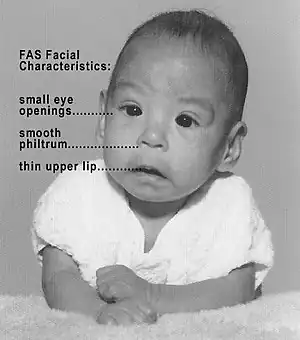

| Baby with fetal alcohol syndrome, showing some of the characteristic facial features | |

Facial features

Several characteristic craniofacial abnormalities are often visible in individuals with FAS.[25] The presence of FAS facial features indicates brain damage, although brain damage may also exist in their absence. FAS facial features (and most other visible, but non-diagnostic, deformities) are believed to be caused mainly during the 10th to 20th week of gestation.[26]

Refinements in diagnostic criteria since 1975 have yielded three distinctive and diagnostically significant facial features known to result from prenatal alcohol exposure and distinguishes FAS from other disorders with partially overlapping characteristics.[27][28] The three FAS facial features are:

- A smooth philtrum: The divot or groove between the nose and upper lip flattens with increased prenatal alcohol exposure.

- Thin vermilion: The upper lip thins with increased prenatal alcohol exposure.

- Small palpebral fissures: Eye width decreases with increased prenatal alcohol exposure.

Measurement of FAS facial features uses criteria developed by the University of Washington. The lip and philtrum are measured by a trained physician with the Lip-Philtrum Guide,[29] a five-point Likert Scale with representative photographs of lip and philtrum combinations ranging from normal (ranked 1) to severe (ranked 5). Palpebral fissure length (PFL) is measured in millimeters with either calipers or a clear ruler and then compared to a PFL growth chart, also developed by the University of Washington.[30]

Ranking FAS facial features is complicated because the three separate facial features can be affected independently by prenatal alcohol. A summary of the criteria follows:[21][31]